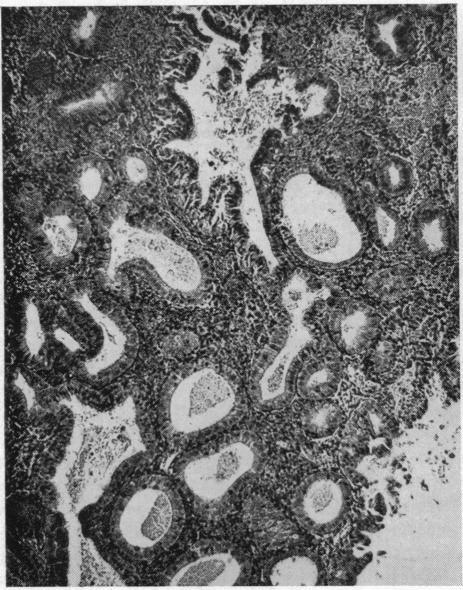

CARCINOMA OF THE ENDOMETRIUM.

Calif Med. 1963 Oct;99(4):252-7.